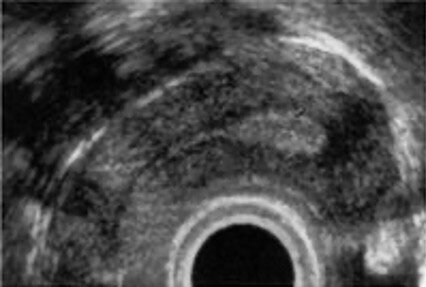

Gebärmutterdarstellung im Ultraschall von der Scheide aus

Gynäkologische Ultraschalluntersuchung

Mittels modernster Ultraschalltechnologie unter ergänzendem Einsatz der Farb-Dopplersonografie können von der Scheide aus (Transvaginal-Ultraschall) oder über die Bauchdecke (Transabdominal-Ultraschall) unter anderem die Gebärmutter und die Eierstöcke dargestellt werden. Ziel ist es, etwa Myome zu erkennen, genauer zu lokalisieren und ihr Wachstum zu beurteilen. Auch die Veränderungen der Gebärmutterschleimhaut lässt sich so erfassen oder wir kontrollieren den Sitz einer Spirale. Ferner sind wir in der Pränataldiagnostik und Schwangerenambulanz mit der fortschrittlichen Technologie in der Lage, möglicherweise gutartige oder bösartige Veränderungen der Eierstöcke frühzeitig zu erkennen und entsprechende Maßnahmen einzuleiten. Diese Untersuchung bietet auch eine wichtige Entscheidungshilfe für oder gegen eine Operation.